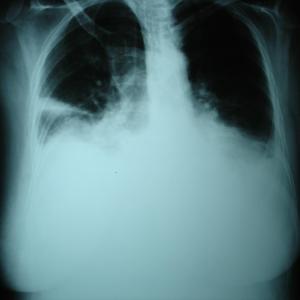

Multimorbidity, frailty up risk of COPD readmission

Frailty and multimorbidity may increase the likelihood of being readmitted within 30 days following an index admmission among patients with chronic obstructive pulmonary disease (COPD), reveals a Singapore study.